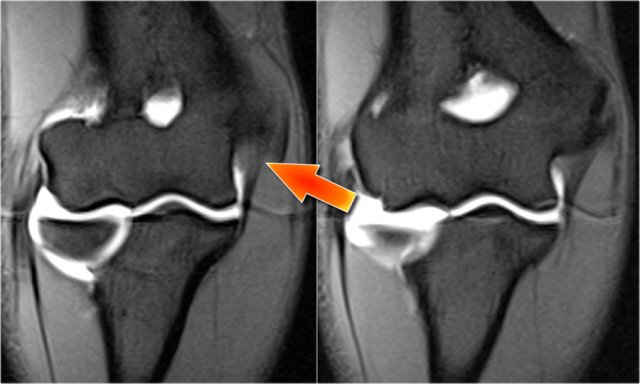

Here we see two consecutive coronal images of the UCL.

It is normal to see some high signal in the proximal part (arrow).

Notice how it firmly attaches to the sublime tubercle and compare this to the next images.

UCL tear

Remember that the UCL should attach very tightly on the sublime tubercle.

In this case it doesn't, so even on these two images you can tell that there is a complete tear.

Notice that there is some marrow edema in the sublime tubercle.